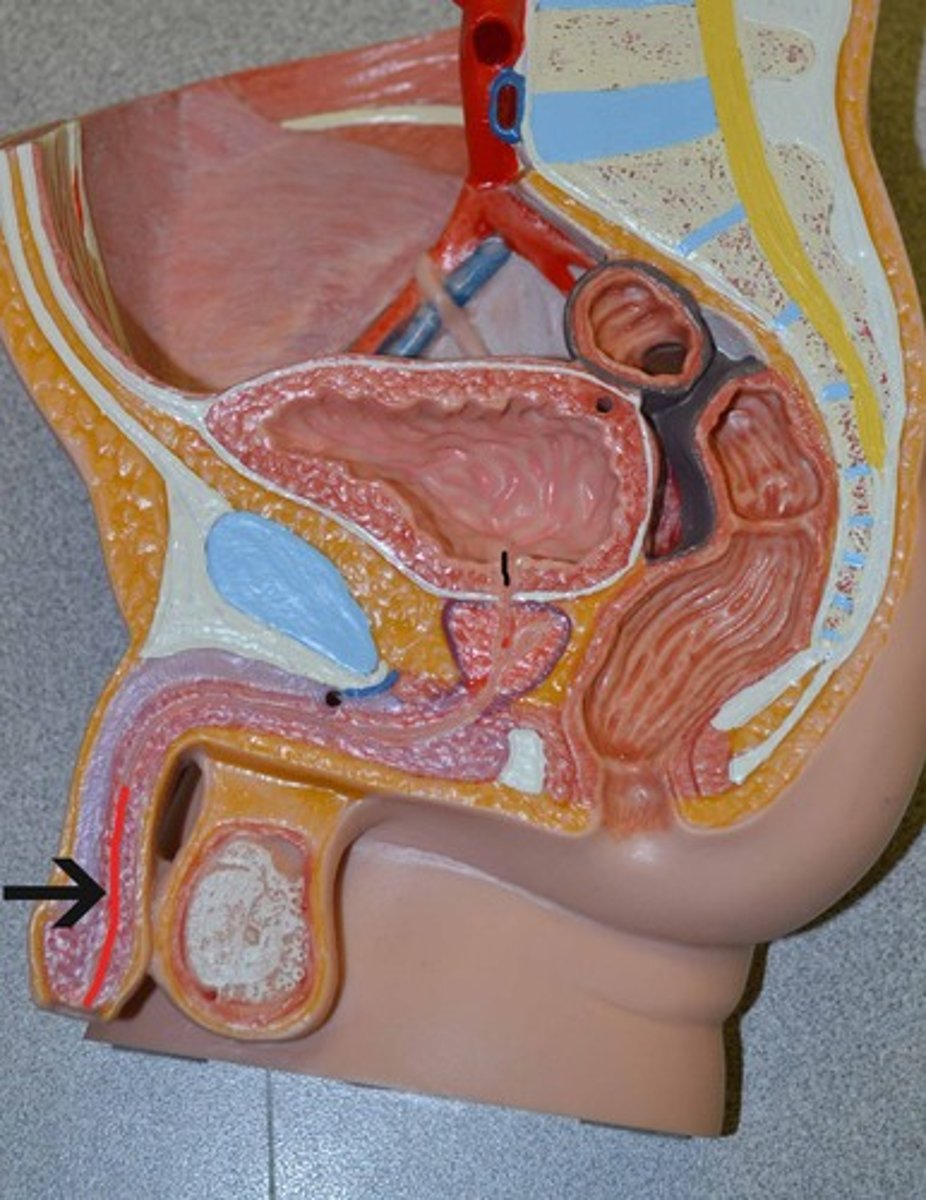

Chapter 30 Anat Phys: Male Reproductive System

Penis

Erectile tissue

Corpus cavernosum

Corpus spongiosum

Spongy urethra